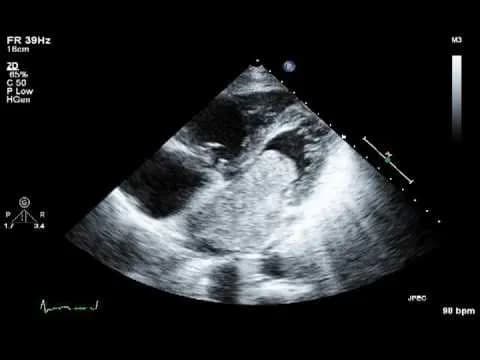

- Siêu âm tim: Đây là phương pháp chẩn đoán hình ảnh quan trọng nhất, giúp xác định vị trí, kích thước, hình dạng và mức độ di động của khối u. Siêu âm tim qua thực quản (TEE) cho hình ảnh rõ nét hơn so với siêu âm tim qua thành ngực (TTE).